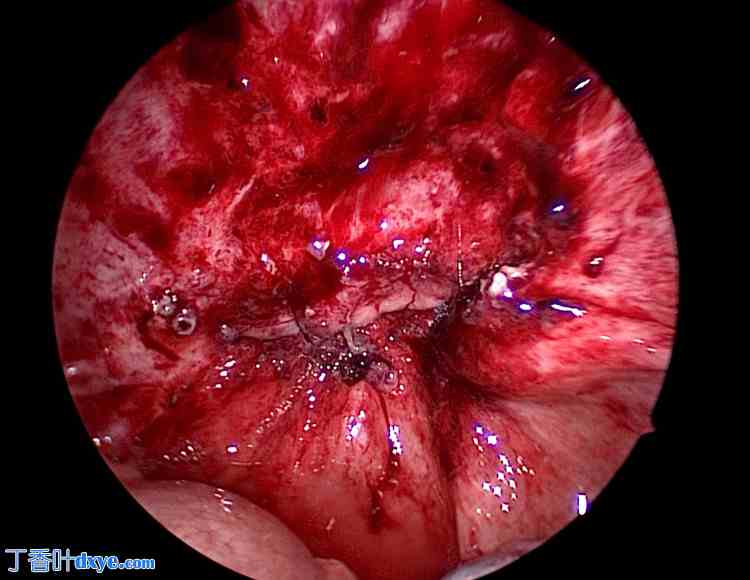

患者在接受全子宫切除术(TLH)后被诊断为阴道阴道炎(VCD)。初始治疗包括抗生素治疗,感染控制后进行再次缝合。入院当天开始经验性给予头孢美唑(2 g/天),疗程7天,阴道培养结果显示为化脓性链球菌。在确认实验室检查结果改善且腹膜刺激症状消退后,于入院第8天行腹腔镜辅助经阴道阴道缝合术。术中,小肠覆盖于阴道残端,并观察到部分阴道残端(黄色箭头)与小肠(浅蓝色箭头)之间存在粘连(图5)。

图5. 阴道残端粘连。